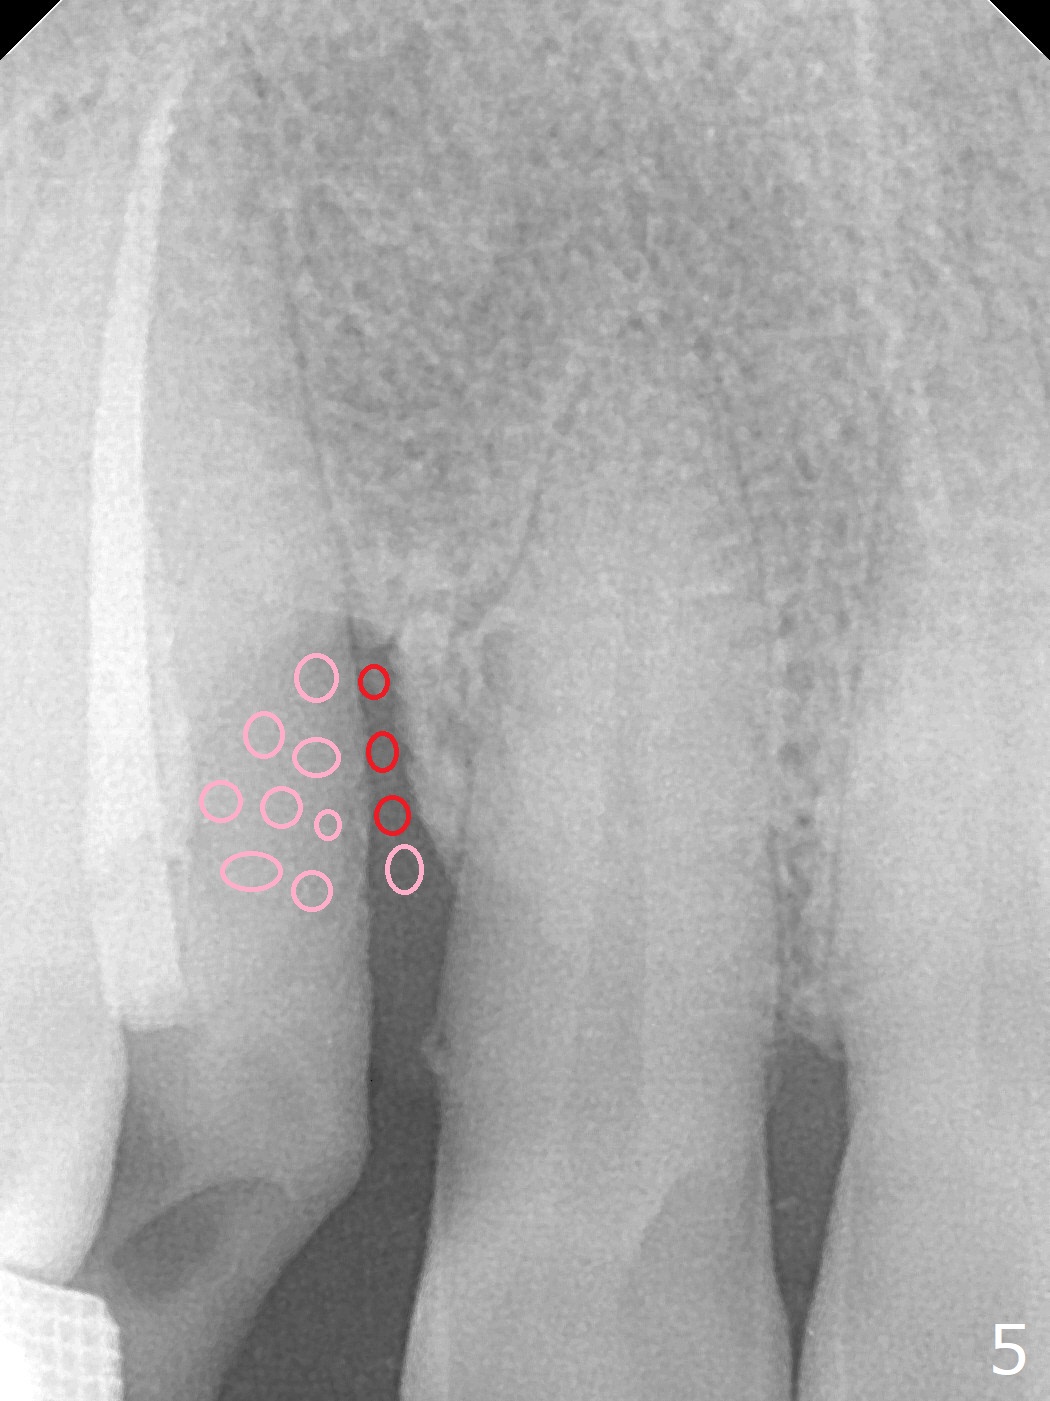

A 62-year-old man had traumatic root fracture at #6 in his teen. The tooth remained asymptomatic until his fifties. Following root canal therapy (Fig.1), the tooth is orthodontically extruded (~ 5 years, Fig.2 (*: bracket)) with apparent disappearance of the infection. The bone distal to #7 seems to increase in height (Fig.3, as compared to Fig.1) and in density (Fig.4). Bone graft could be placed for regeneration with PRF or GEM21S (Fig.5 red (between #6 and 7), pink (buccal to #7 or coronal to the fracture line) circles). With extrusion, the oblique fracture line is more than half or two third supragingival (Fig.6). In spite of severe bone loss, exostosis is present (Fig.7 (mesiobuccal view) E) so that bone graft could be placed palatal to it (Fig.8 red). In case the tooth is non-salvageable, immediate implant will be placed with guide (Fig.9,10). Move lingual button as apical as possible (Fig.12) and make occlusal clearance. Continue extrusion until all of the crack is exposed without deep pocket.